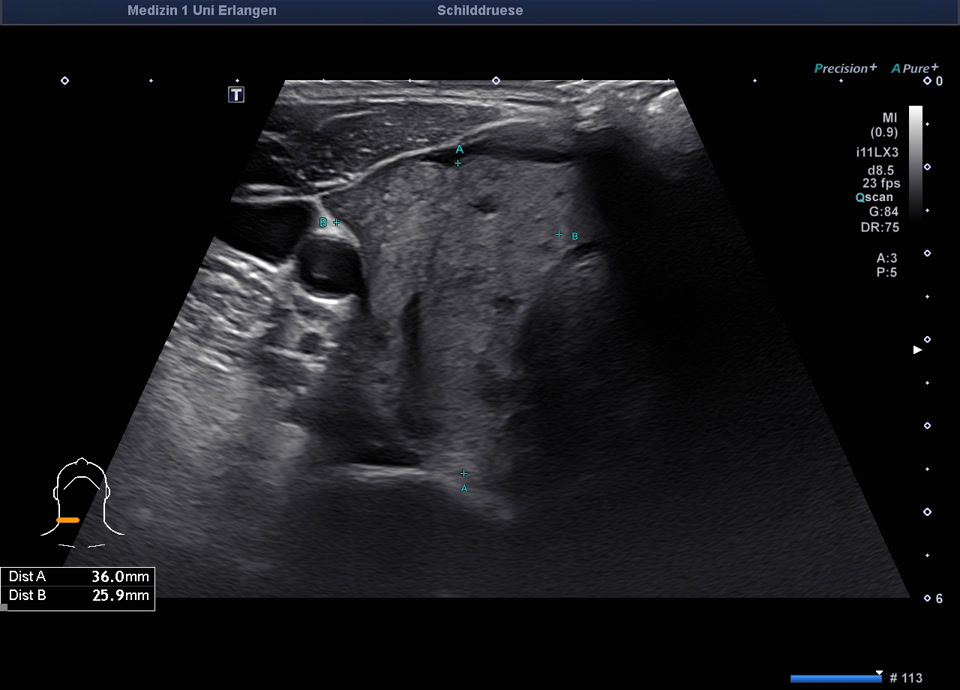

45-year-old male presented patient with persistent sore throat and general symptoms following an EBV-infection. An external diagnosis of post-infectious de Quervain’s thyroiditis had already been made, and a two-week course of corticosteroid therapy was administered. Initial clinical improvement with reduced throat pain was noted under treatment, but symptoms reoccurred after discontinuation of corticosteroids. Laboratory findings revealed leukocytosis of 12,000/µl and CRP of 113 mg/l. Sonographically, a bilaterally enlarged thyroid gland with diffusely hypoechoic areas and inhomogeneous parenchyma was observed. Combined with the patient history, this was characteristic of a subacute thyroiditis with relapse after short-term corticosteroid therapy. Prolonged corticosteroid therapy with slow tapering was performed. Under this regimen, marked clinical improvement occurred within weeks; follow-up ultrasound four months later showed a normal-sized thyroid with only mildly inhomogeneous parenchyma, consistent with resolving thyroiditis.